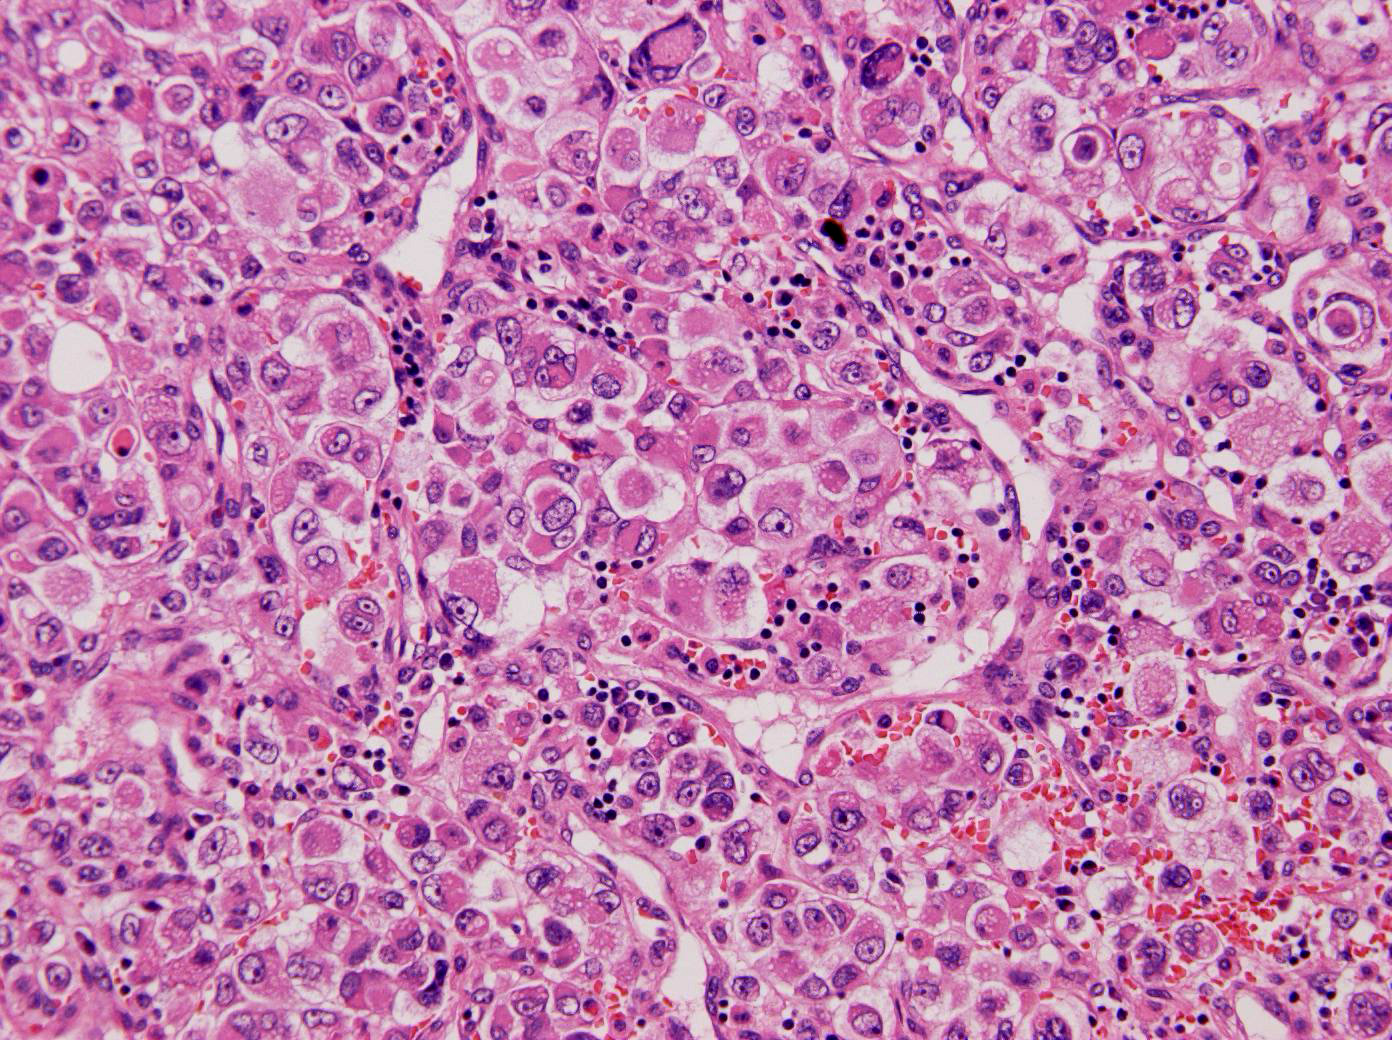

腫瘍細胞は大型で,好酸性の胞体を持ち,多形性に富み,細胞結合は緩く,肉腫様にみえた.免疫組織ではLCA,CD20,CD79a,CD3,CD45RO,CD30,S-100蛋白はいずれも陰性で,AE1/AE3とEMAが陽性であった.

Renal cell carcinoma, sarcomatoid carcinoma (WHO: RCC, unclassified).会場からrhabdoid cell typeのRCCという意見が出た.免疫組織が診断の手がかりになった症例であるが,組織も毛細血管に囲まれた充実性胞巣を示すなど,腎細胞癌の特徴を示している.本症例は凝固抑制第8因子が1,570BU/ml,凝固抑制第9因子が12BU/mlと高く,renal cell carcinomaに併発した後天性血友病であり,血液内科学的にも珍しい症例であった. |